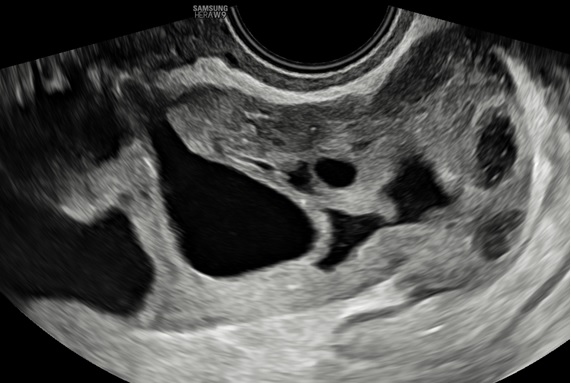

– Siêu âm: Tử cung và 2 buồng trứng bình thường. Ở cùng đồ sau có cấu trúc echo kém không đồng nhất dạng hình ống, có vách ngăn dày thông nhau, kích thước # 84x 89x 37 mm, bờ trong thành u không trơn láng, bên trong có nhiều mảng echo kém dạng mô đặc, tăng sinh mạch máu mức độ 2. Bụng và cùng đồ: không dịch.

– Chẩn đoán siêu âm: Huyết tụ thành nang. Chẩn đoán khác: áp xe phần phụ.

Hình 4: Siêu âm ngã âm đạo thang xám cho thấy khối u hình ống ở cùng đồ sau nhiều vách ngăn dày thông nhau.